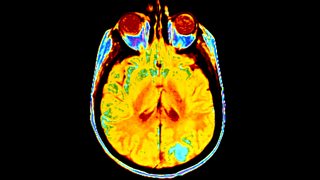

Recalling the Past

3/5Ben Silburn discovers how our brain's neural network creates and stores memories.